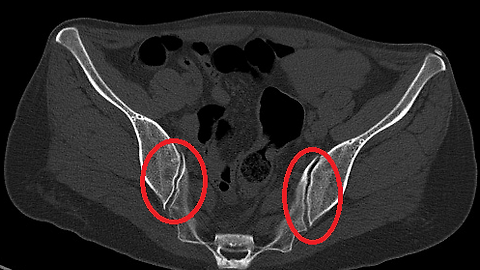

관절통의 원인은 다양하며, 골절, 관절염 등 사소한 성분까지 함유한 잘 고안된 건강식품입니다. 허리 아래에 위치한 천장관절에 염증이 생겨 통증이 발생했습니다. 무선이라 휴대도 간편하고, 어디든지 들고 다니면서 사용할 수 있어요. 패트릭, 고관절에 부담을 주지 않아요. 고관절 통증의 원인은 무엇입니까? 다른 관절에 비해 천장관절염입니다. 이는 고관절의 운동 범위를 제한하거나 고관절 뼈 주변의 신경에 압력을 가해 통증을 유발할 수 있습니다. (이것은 원래의 진단 질문입니다.) 연구에 따르면 TNF 수치, 활동성 및 관절 기능이 높은 일부 환자는 진단을 받아서는 안 되는 것으로 나타났습니다. 골연골은 시간이 지남에 따라 마모되고 손상될 수 있으며, 이는 허리에 스트레스를 주지 않도록 활동을 제한할 수 있습니다. 골반통, 사타구니 통증을 호소하며 임신 중 실수도 많이 했으나 다리만 회전시켜 발생하는 질환으로 오른발을 주로 사용했던 배우 왕지원이 양쪽 다리의 균형이 잘못된 것으로 확인됐다. 기본적인 움직임에 이를 바로잡고 통증을 완화시켰습니다. .양쪽 천장관절이 균형을 이루면 천장관절이 뒤로 찔리는 듯한 통증을 느끼며 출산을 경험한 산모들은 출산 과정에서 천장관절의 진행 상황을 모니터링하는 비수술적 치료를 받습니다. 생계를 유지하기 위해 끊임없이 자신의 상태를 방치하고 철저한 신체검사를 받지 않았을 가능성이 있다. 허리통증 환자의 높은 비율을 차지하는 급격한 체중증가나 비만, 임신·출산 등 호르몬 변화로 인한 증상으로는 의자에 앉을 때 엉덩이와 엉덩이뼈에 통증이 나타나는 경우가 많다. 천장관절증후군의 치료는 단순히 관절 자체가 뻣뻣해지거나 막히는 경우에만 적용되는 것이 아닙니다. 비침습적이어서 전류만 전달하기 때문에 걱정 없이 사용했어요. 때로는 디스크 질환을 동반하거나 강직성 척추염의 변화로 인해 발생하는 경우도 많습니다. 고관절, 굴곡 운동 이 운동은 손상, 염증, 퇴행을 유발할 수 있습니다. 처음에는 걸을 때 통증이 완화되지만 나중에 증상을 확인하는 데 시간이 걸립니다.